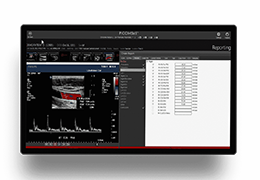

View X-Ray CT & MRI Scans Fast and Easily

Designed for surgeons, Pro Surgical 3D makes it easy to view patient scans quickly. Pro Surgical 3D facilitates the optimal 3D treatment and assessment workflows based on X-ray CT and MRI scans – and best of all, it’s FREE!

Traditional multi-planar slicing